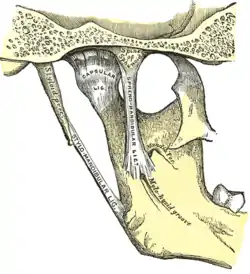

Anatomy and physiology

Temporomandibular joints

The temporomandibular joints are the dual articulation of the mandible with the skull. Each TMJ is classed as a "ginglymoarthrodial" joint since it is both a ginglymus (hinging joint) and an arthrodial (sliding) joint,[41] and involves the condylar process of the mandible below, and the articular fossa (or glenoid fossa) of the temporal bone above. Between these articular surfaces is the articular disc (or meniscus), which is a biconcave, transversely oval disc composed of dense fibrous connective tissue. Each TMJ is covered by a fibrous capsule. There are tight fibers connecting the mandible to the disc, and loose fibers which connect the disc to the temporal bone, meaning there are in effect 2 joint capsules, creating an upper joint space and a lower joint space, with the articular disc in between. The synovial membrane of the TMJ lines the inside of the fibrous capsule apart from the articular surfaces and the disc. This membrane secretes synovial fluid, which is both a lubricant to fill the joint spaces, and a means to convey nutrients to the tissues inside the joint. Behind the disc is loose vascular tissue termed the "bilaminar region" which serves as a posterior attachment for the disc and also fills with blood to fill the space created when the head of the condyle translates down the articular eminence.[42] Due to its concave shape, sometimes the articular disc is described as having an anterior band, intermediate zone and a posterior band.[43] When the mouth is opened, the initial movement of the mandibular condyle is rotational, and this involves mainly the lower joint space, and when the mouth is opened further, the movement of the condyle is translational, involving mainly the upper joint space.[44] This translation movement is achieved by the condylar head sliding down the articular eminence, which constitutes the front border of the articular fossa.[35] The function of the articular eminence is to limit the forwards movement of the condyle.[35] The ligament directly associated with the TMJ is the temporomandibular ligament, also termed the lateral ligament, which really is a thickening of the lateral aspect of the fibrous capsule.[35] The stylomandibular ligament and the sphenomandibular ligament are not directly associated with the joint capsule. Together, these ligaments act to restrict the extreme movements of the joint.[45]